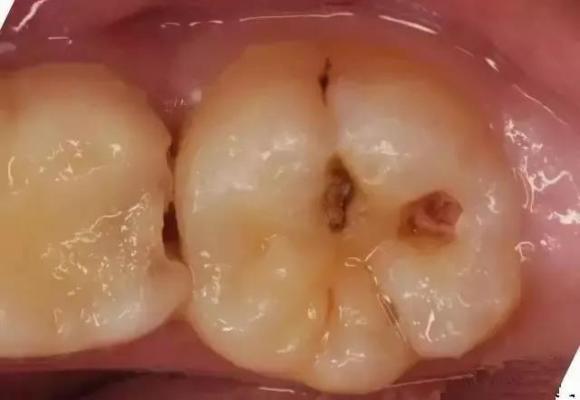

18730692647 严重龋齿、突发牙齿创伤、慢性牙齿磨耗……,这些都有可能使我们的牙齿变得不完整,甚至导致牙体硬组织大部分或者接近完全丧失,形成残冠、残根。很多人觉得口内残冠残根既影响美观又不舒适,恨不能一拔了之,但拔掉之后还要去镶牙,岂不是更麻烦?到底是“留”还是“拔”,这成为众多患者共同纠结的问题。

残根残冠会成为口内潜在感染源。长时间嵌塞食物令残根残冠处成为细菌滋生繁殖的地方,不仅容易引发口腔异味,还会引发牙龈炎、牙周炎等局部感染性口腔疾病。严重的牙周炎有时会从病灶处蔓延到邻近的牙齿,导致邻近牙齿的炎症或松动。

牙体长时间缺损还可造成咬合紊乱,引起邻近牙齿的移位和对颌牙的伸长,降低咀嚼功能并可能引发颞下颌关节紊乱。牙体缺损若形成锐利牙尖,反复摩擦舌、颊处口腔黏膜及软组织,则会引起反复的创伤性溃疡,甚至是经久不愈的溃疡。更为严重的是,锐利的牙尖不断损伤口腔黏膜,成为长期慢性不良刺激,可能成为一个致癌的因素(如引起舌癌、颊癌)。

应根据牙齿情况及时修复残冠残根